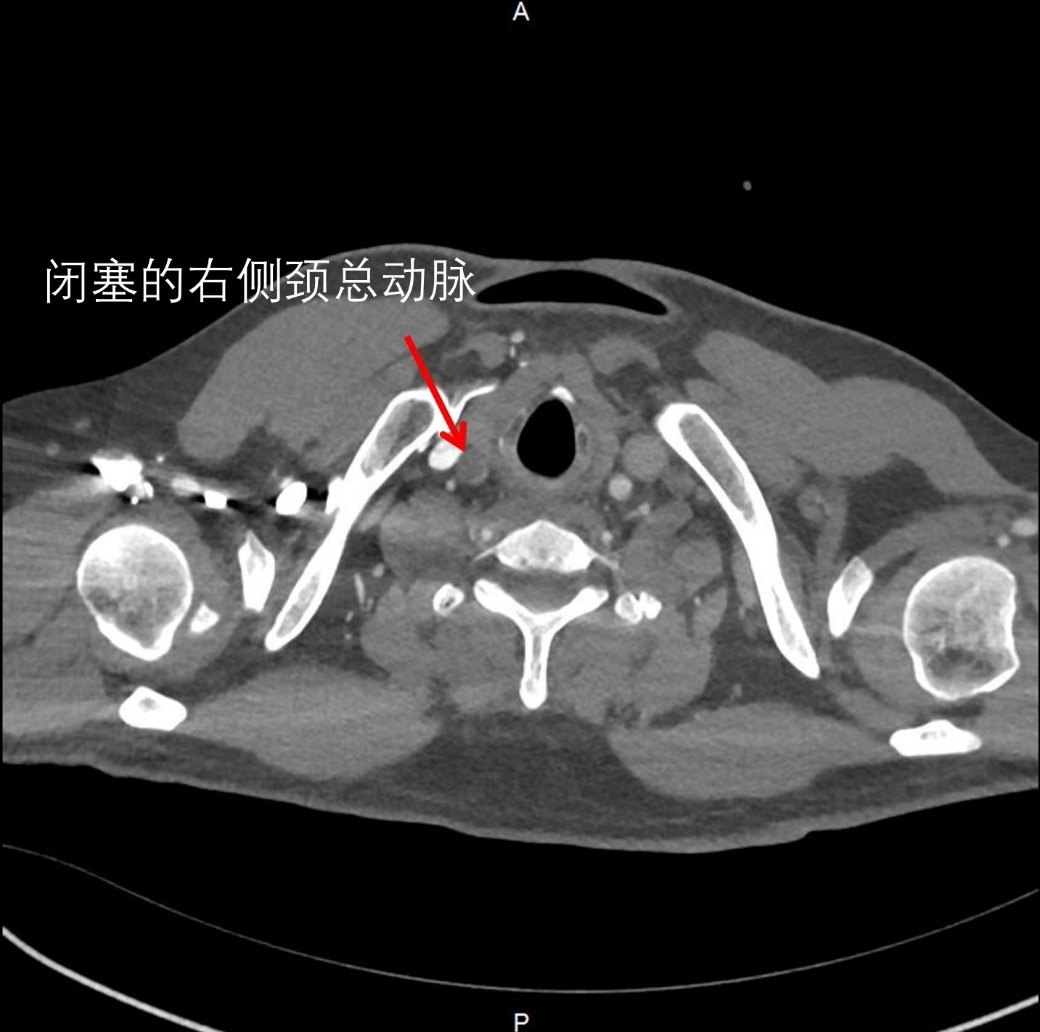

11月初的深夜,一位60岁左右的男性患者因突发胸背部剧烈疼痛被送往新华医院奉贤院区急诊。主动脉CTA检查结果显示,患者确诊为A型主动脉夹层,夹层范围从心脏根部延伸至胸、腹部及下肢,更危急的是,夹层已累及供应右侧大脑的右颈总动脉,导致血管完全闭塞,右侧大脑血供中断。

图2: 供应右侧大脑血供的大动脉被夹层挤压闭塞